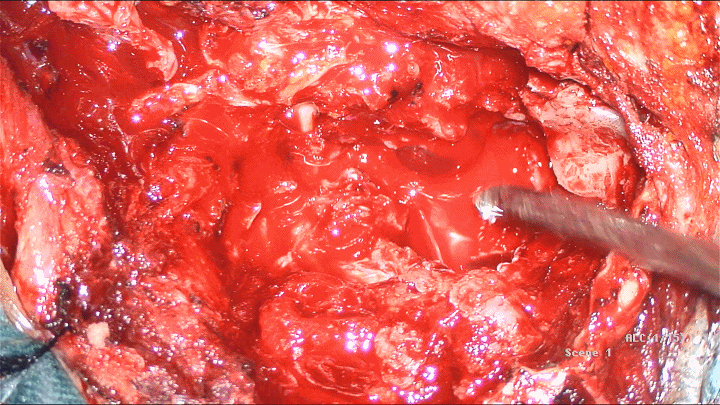

3.切除CPA区肿物↑↑↑↑可见面神经中枢端被破坏